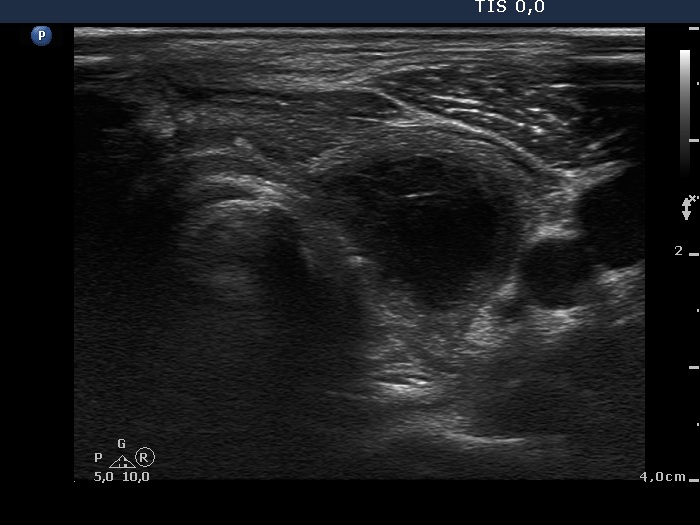

Examination before surgery (first row of images):

Clinical data: A 21-year-old woman requested a second opinion. She has been treated for Graves' hyperthyroidism for three years. The hyperthyroidism relapsed two times. She suffered from mild exophthalmos and occasionally diplopia. Actually, she had no complaints.

Palpation: The thyroid lobes were enlarged. There were no palpable nodules.

Result of blood test: subclinical hyperthyroidism on daily 15 mg methimazole therapy (TSH 0.001 mIU/L, FT4 12.9 pM/L, FT3 4.11 pM/L).

Ultrasonography. The thyroids were echonormal and contained hypoechogenic discrete areas none of them corresponded to a nodule. The echogenicity index was around 30%. The vascularization was average.Surgery was advised. Total thyroidectomy was performed. Histopathology disclosed diffuse goiter, focal lymphocytic thyroiditis.